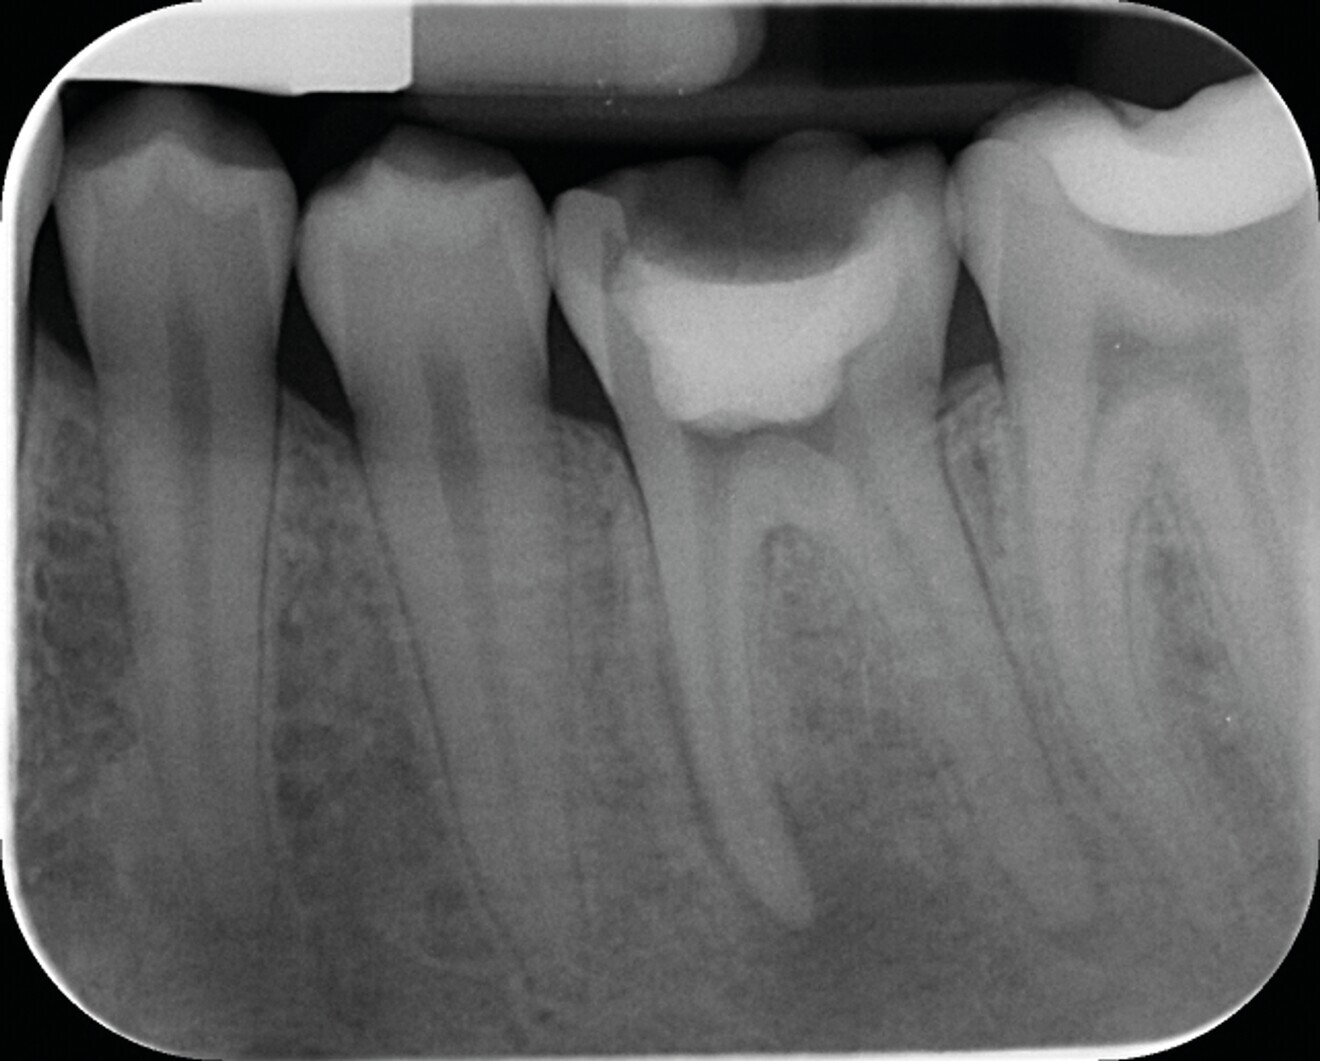

Fig. 6a : Exemple de traitement canalaire réalisé avec des instruments et techniques d’obturation de dernière génération : (a) radiographie préopératoire d’une molaire maxillaire présentant une nécrose pulpaire.

Fig. 6b : Radiographie postopératoire du traitement canalaire – mise en forme avec le système BlueShaper (Zarc – Endoboutik), désinfection avec hypochlorite de sodium activé avec Irriflex (Produits Dentaires) et obturation en compaction verticale de gutta chaude.